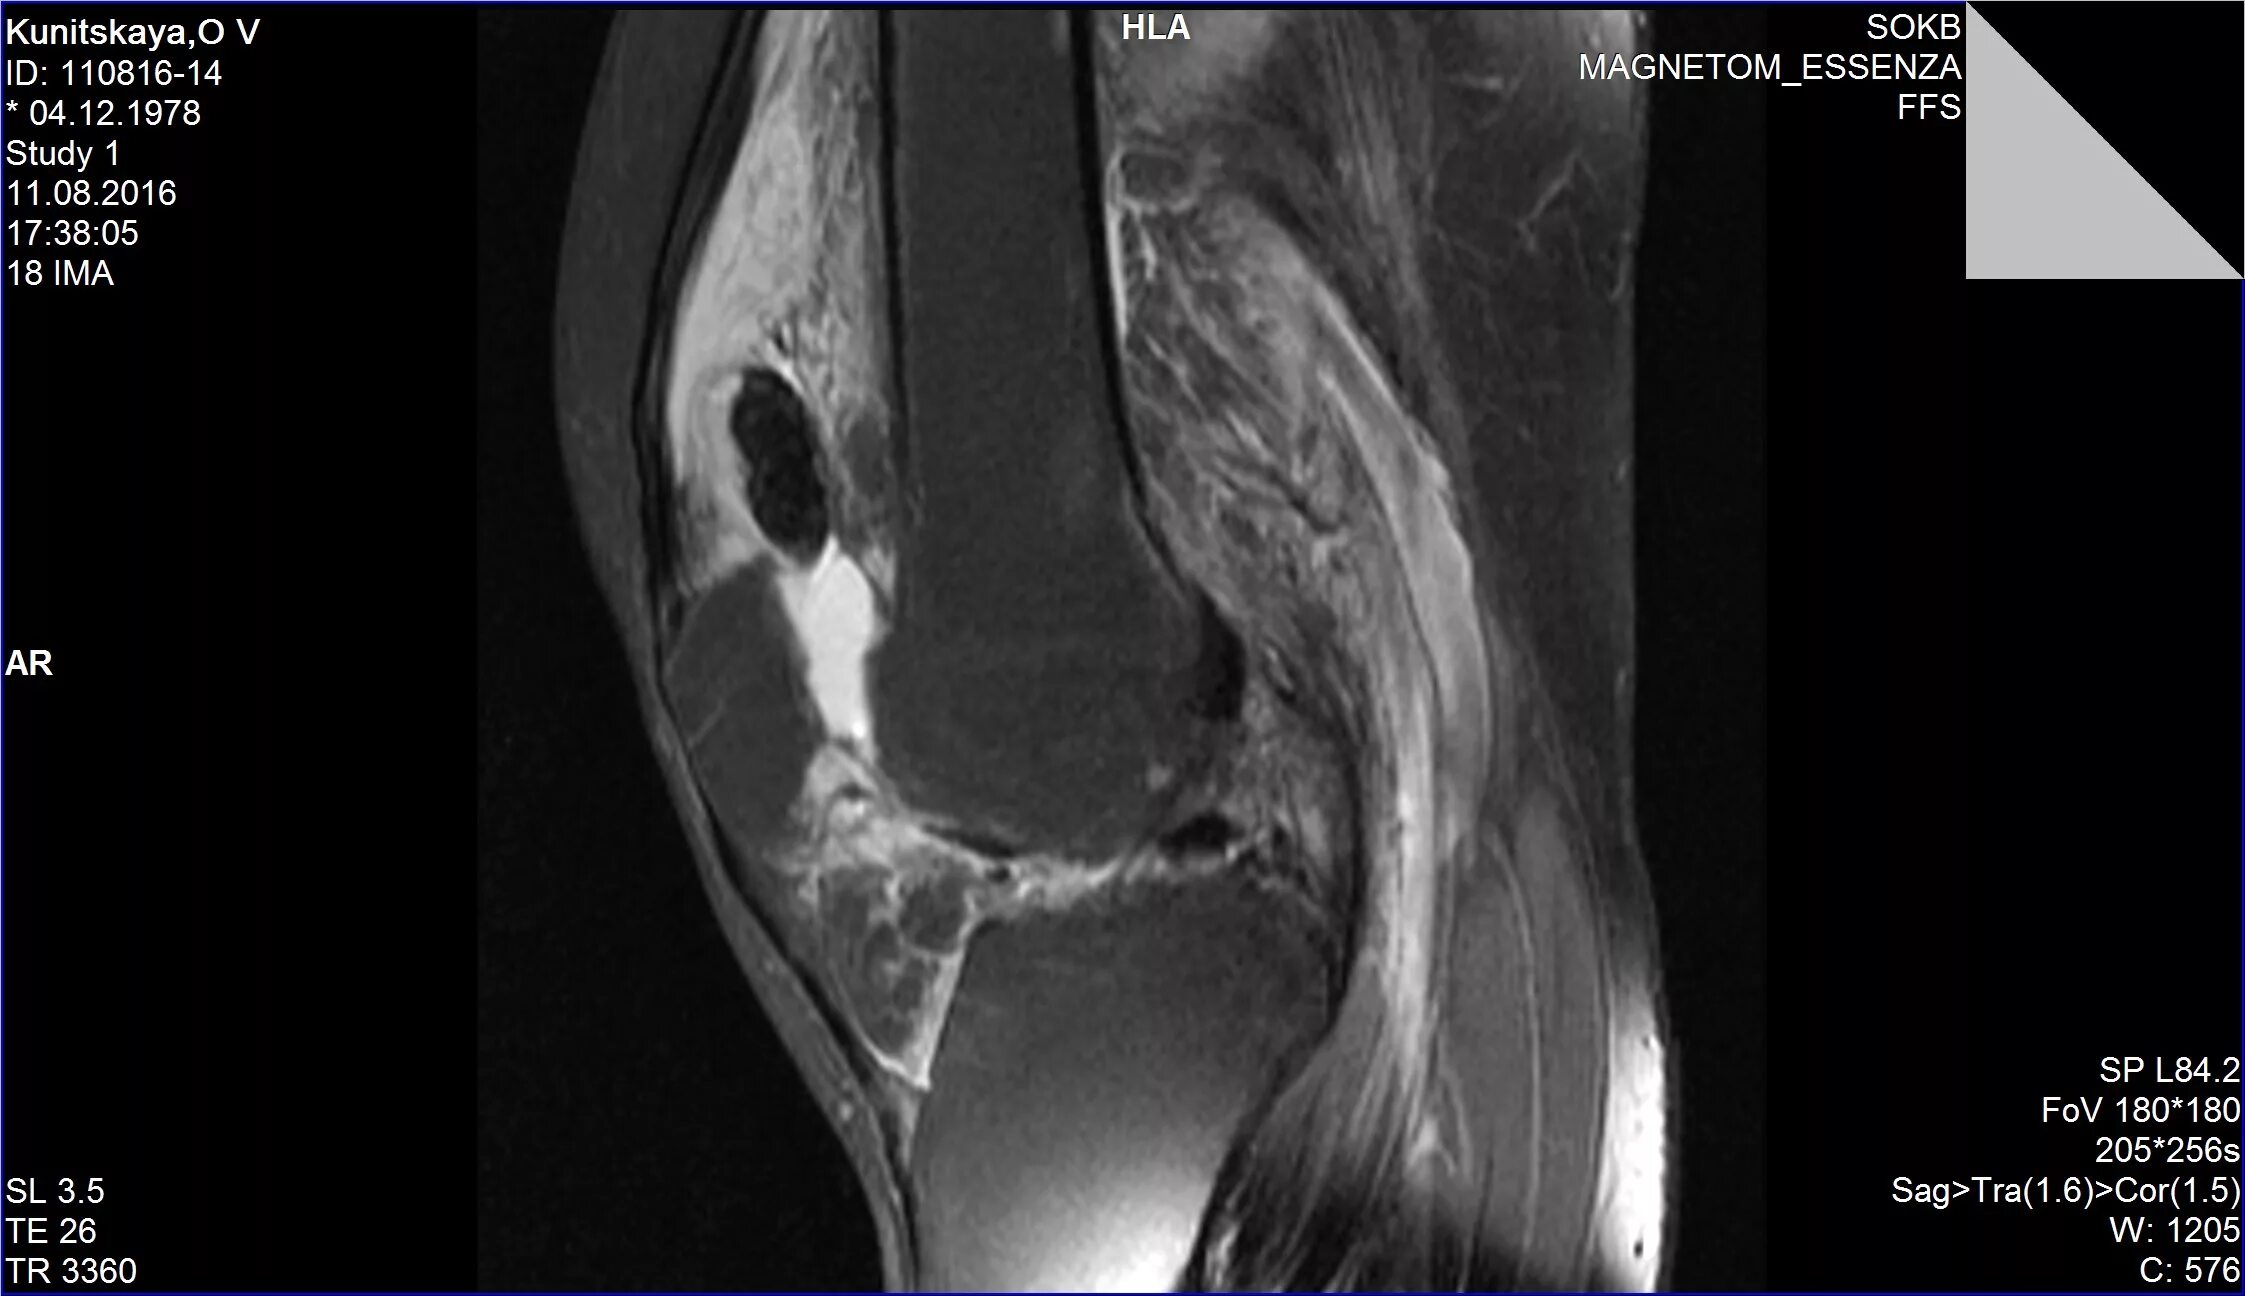

Пигментный виллонодулярный синовит